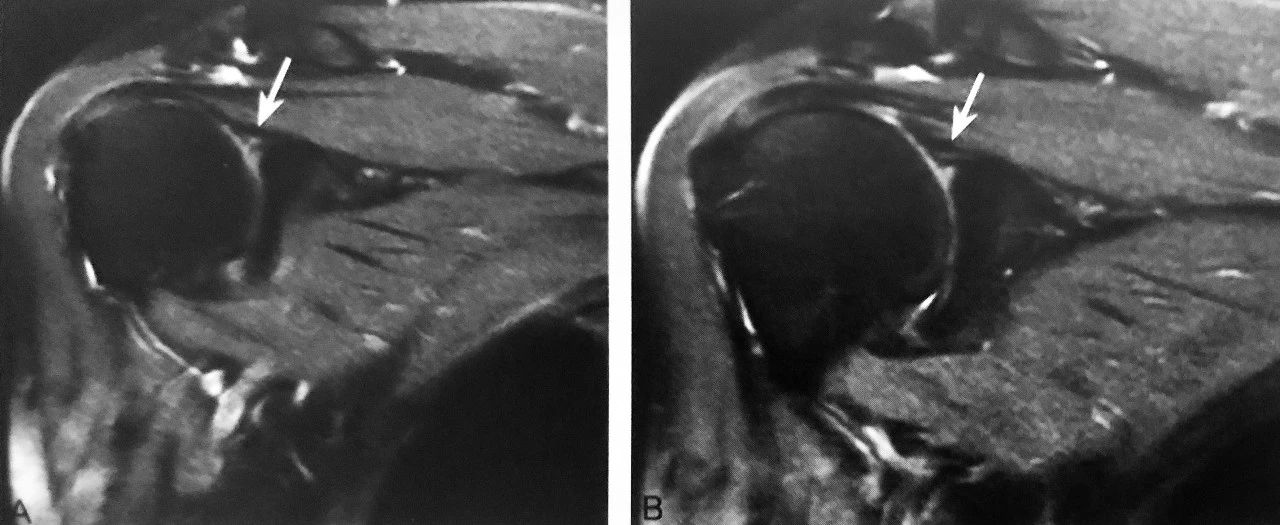

双肩锁关节征:A 图冠状位压脂 PD 序列显示,肩峰关节面下可见游离的条状、未融合肩缝小骨(箭头),肩锁关节囊积液,伴肩峰下-三角肌下滑囊积液,同时可见冈上肌肌腱撕裂(三角);B 图矢状位压脂 PD 序列显示:未融合肩峰小骨与肩峰关节面、肩锁关节形成双肩锁关节,肩锁关节囊积液,伴肩峰下-三角肌下滑囊积液(箭头)

判读要点:

1、在肩关节 MRI 冠状位或矢状位观察;

2、须同一层面同时观察到肩锁关节及肩峰小骨;

3、注意双肩峰关节征与第二肩锁关节区别;

4、观察肩峰小骨是否稳定,如不稳定,是否与邻近软组织产生撞击,此时应注意观察是否伴有周围积液、水肿、肩锁关节损伤及肩袖损伤。